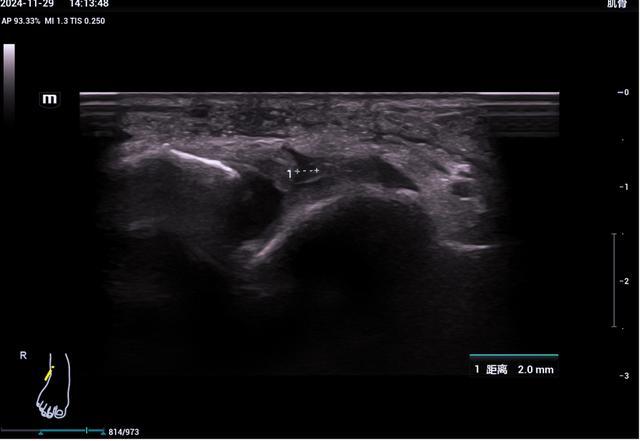

▲距腓前韧带断裂

(III°损伤)

6、踝关节超声检查

踝管综合征、跟腱断裂、跟腱止点炎、崴脚后所致韧带损伤(距腓前韧带、跟腓韧带、胫腓前韧带、胫腓后韧带、距腓后韧带)、腓骨长短肌损伤、跖腱膜纤维瘤样增生、足底筋膜炎、痛风性关节炎等。